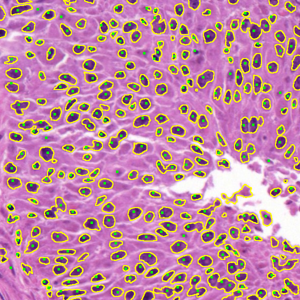

Dataset 1 comprises a synthetic video and two hematoxylin and eosin (H&E)-stained images collected from public online sources [71, 72]. H&E staining is standard in histopathology, with nuclei appearing blue–purple and cytoplasm pink. The images are provided in RGB format with varying image sizes and are used solely for qualitative illustration and timing comparisons, as no ground-truth annotations are available. The synthetic video consists of 74 MATLAB-generated frames. The first frame shows a 3D mitochondrial mesh generated via the isosurface function and rendered with Phong illumination, with the light source positioned above and to the right of the camera. Subsequent frames are obtained by rotating this initial view. This dataset was constructed to study segmentation under pronounced frame-to-frame illumination changes.

Dataset 2, released as supplementary material in [73], contains 36 digitized H&E-stained microscopy images (600 × 600 pixels) with 7931 nuclei annotated by three expert pathologists; only consensus annotations are retained. It is designed for cell nuclei detection.

Representative samples from the three datasets are shown in Fig. 1. In (a), the first frame of the synthetic video in Dataset 1 illustrates the strong illumination gradients produced by distance-dependent shading together with orientation-dependent interactions between vertex normals and the light direction. The H&E images in (b) and (c), also from Dataset 1, depict a mast cell infiltrate from a patient with non-alcoholic steatohepatitis and cirrhosis and, respectively, a sample from a patient with sclerosing polycystic adenosis of the parotid gland; the former consists primarily of purple nuclei, white cytoplasm, and pink extracellular tissue. Subfigures (d) and (e) show two examples from Dataset 2 accompanied by their ground-truth nuclei annotations, while (f) and (g) present a representative image from Dataset 3 together with its corresponding cell mask.

Figure 1: Samples from Datasets 1–3. (a) First frame of the 74-frame video in Dataset 1 (1770 × 880) with a superimposed red mesh. (b,c) H&E-stained tissue images from Dataset 1 (1000 × 750; 950 × 730). (d,e) Cell images from Dataset 2 (600 × 600) with nuclei annotations. (f,g) Image from Dataset 3 (512 × 512) with annotation.